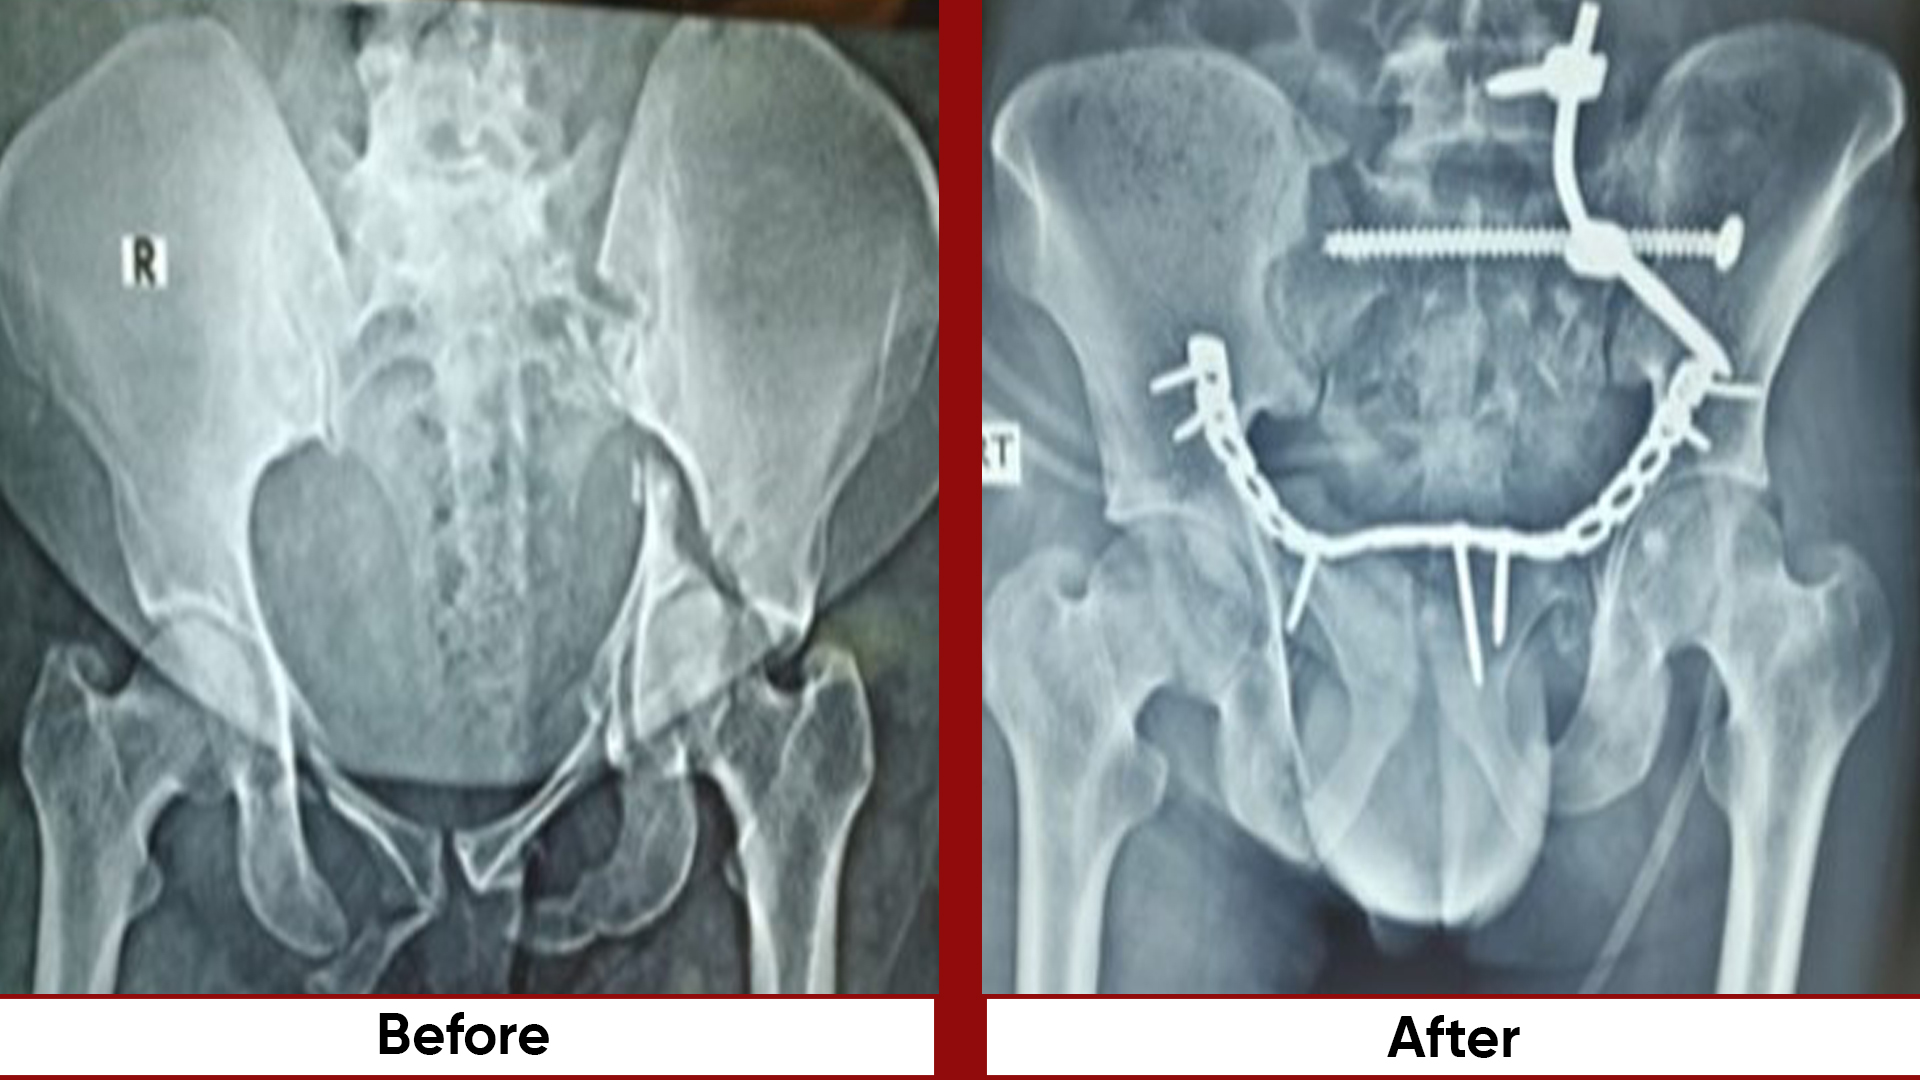

Procedures

• Fracture Management (simple and complex trauma)

• Pelvic & Acetabular Fracture Fixation